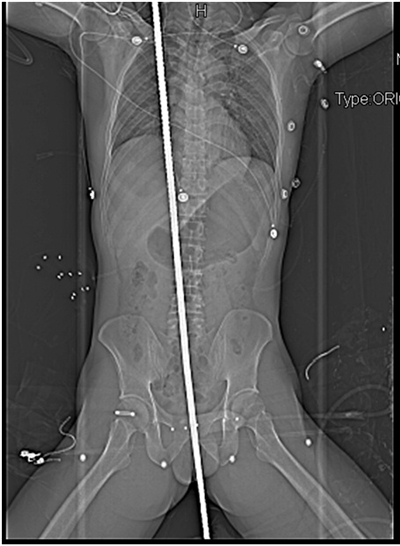

X光片顯示,鋼筋“完美”避開了男子的重要髒器

經過肆川大學華西醫院多個科室約7小時手術,壹名被鋼筋自胯下貫穿身體的男子被送進ICU病房,術後生命體征平穩。

根據醫生描述,該男子可以說遭遇了不幸中的大幸:鋼筋進入其體內後,完美避開了重要髒器,沒有造成大出血,“如果鋼筋向左右歪壹點,男子的性命都有可能不保。”醫生感歎,鋼筋的這種穿插路徑,即使刻意去做都很難做到。

回憶起前晚的那台手術,肆川大學華西醫院胸外科主治醫生馬林感歎:傷者遭遇了不幸中的大幸。當天下午5時左右,壹名37歲男子送到醫院急診科。據稱,該男子在工地上遭遇電擊,隨後落下時坐到壹根長約1.2米的螺紋鋼筋上,鋼筋從距其肛門約1厘米的位置斜插進身體,直抵右肩部位才停下。

“傷者送來時,生命體征平穩,意識也算清醒,只是可能受到了驚嚇。”馬林介紹,他們對傷者做了增強CT後發現,男子的胸腔、腹腔無明顯出血,“整個循環系統的血管沒有明顯損傷。”

該男子的胸腔和腹腔被打開後,在多科醫生的密切注意下,這根直徑近1厘米、長約1.2米的鋼筋被取了出來,隨後醫生對男子的肺、肝髒的受損部位做了切除,並修補了其破損的小腸。

在做了細致處理後,該男子被送進ICU病房。據了解,目前其生命體征平穩。“手術期間傷者壹共出了約500毫升血。”馬林介紹,這比壹次獻血量(400毫升)多100毫升,影響不大。